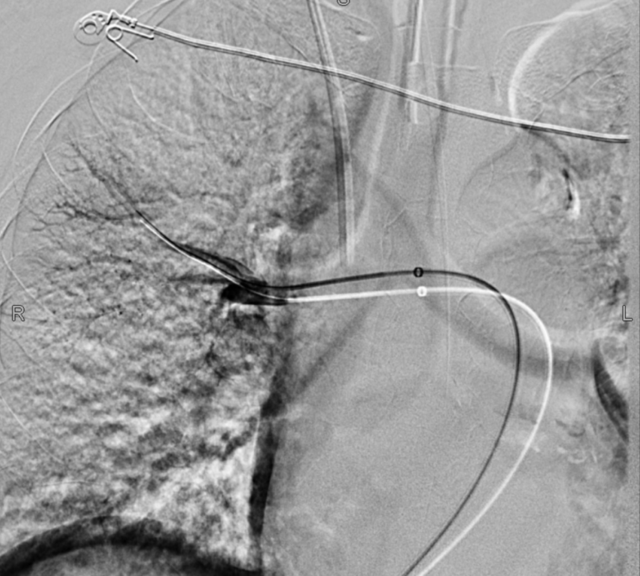

介入团队和呼吸监护室医生在做好预案和家属充分沟通的基础上,李女士在RICU医护的护送下,有创呼吸机转运至放射科完善支气管动脉CTA检查,结果显示右上肺支气管动脉迂曲畸形,疑似有小动脉瘤出血。

介入科钱雪峰、赵震宇医师随即部署安排介入手术,通过造影成功锁定出血血管,并顺利实施右支气管动脉栓塞术+右肺中叶肺动脉分支栓塞术。经介入手术治疗后,李女士的咯血症状明显好转。

▲血管介入手术